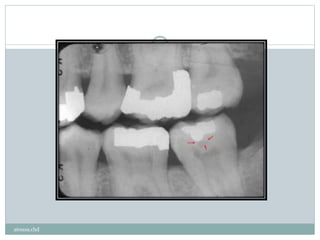

‫یا‬ ‫ثانویه‬ ‫پوسیدگی‬ ‫است‬‫ممکن‬ ‫موجود‬ ‫ترمیم‬ ‫یک‬ ‫لبه‬‫در‬ ‫شده‬ ‫ایجاد‬ ‫پوسیده‬ ‫ضایعه‬ ‫یک‬

‫شود‬ ‫می‬ ‫نامیده‬ ‫کننده‬ ‫عود‬.

‫شود‬ ‫محو‬ ‫ترمیم‬ ‫ادیواپک‬‫ر‬ ‫تصویر‬ ‫بوسیله‬ ‫است‬‫ممکن‬‫ترمیم‬‫ر‬‫مجاو‬ ‫ضایعه‬ ‫یک‬